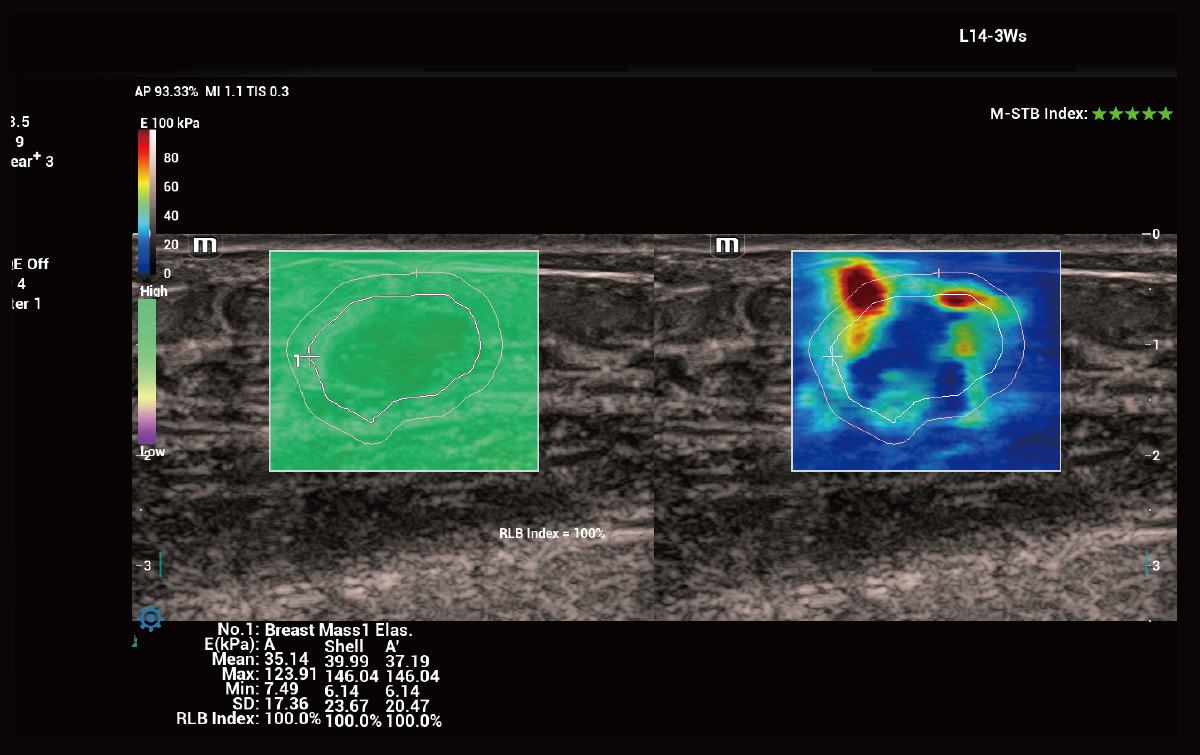

Evaluación de rigidez innovadora – STE

Sound Touch Elastography (STE) ofrece imágenes de elastografía de ondas de corte 2D en tiempo real. Proporciona un análisis cuantitativo basado en la evaluación de la rigidez del tejido.